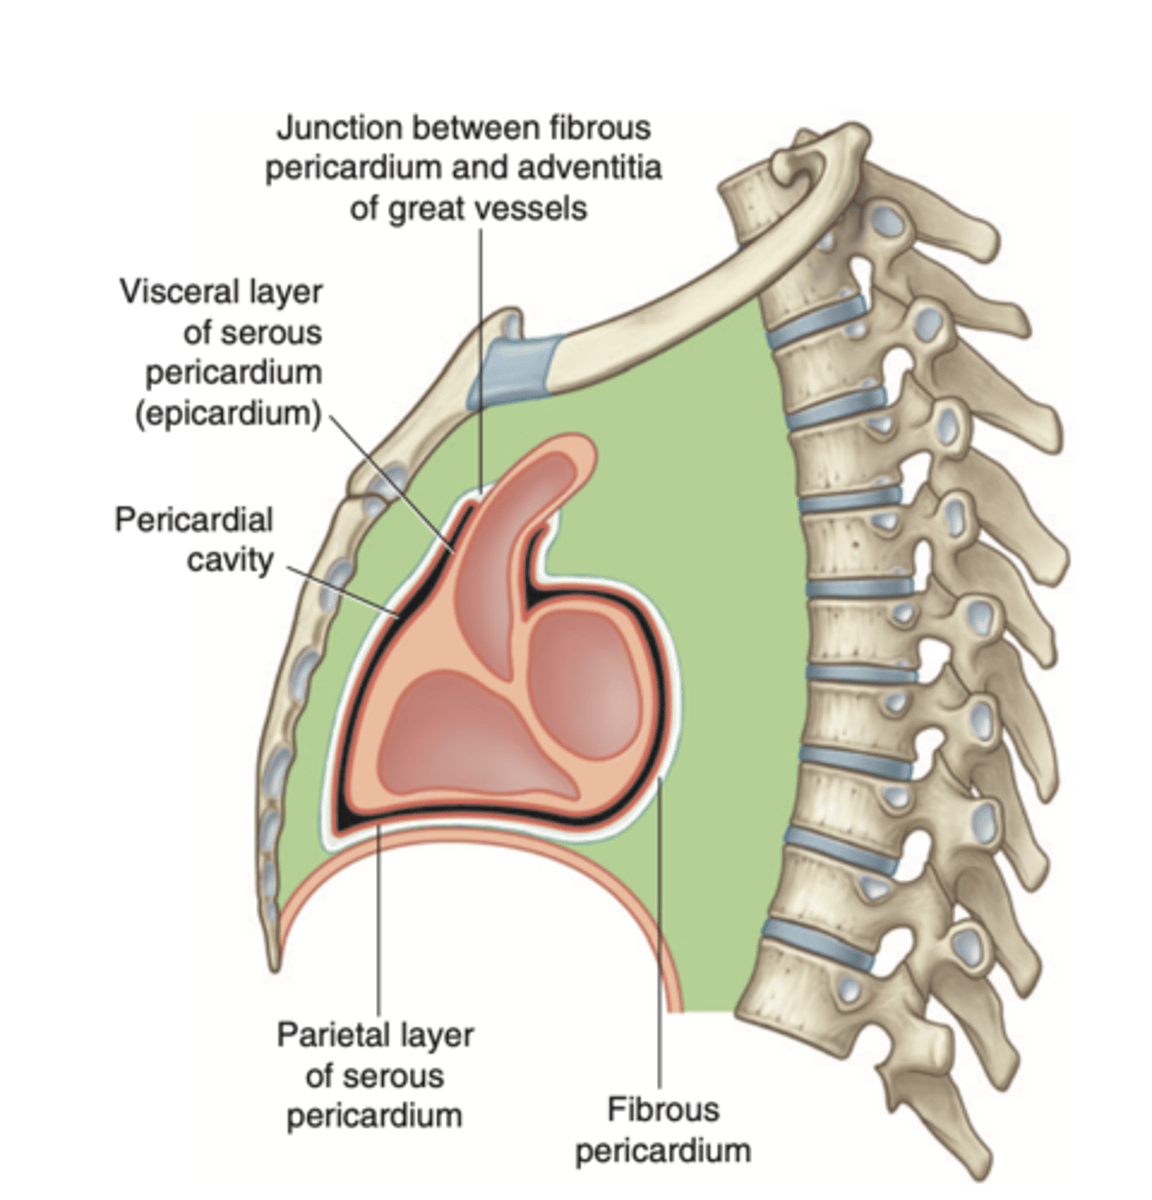

What are the layers of the pericardium?

The pericardium consists of two main layers:

- the fibrous pericardium

- the serous pericardium

How is divided the serous pericardium?

. Visceral layer or Epicardium (innermost). Adheres to the heart

. Parietal layer (outermost)

Between these layers is the pericardial fluid (pericardium cavity )

What is the fibrous pericardium?

the tough, outer layer

protects the heart

maintains its position in the thorax.

defines the boundaries of the medium mediastinum